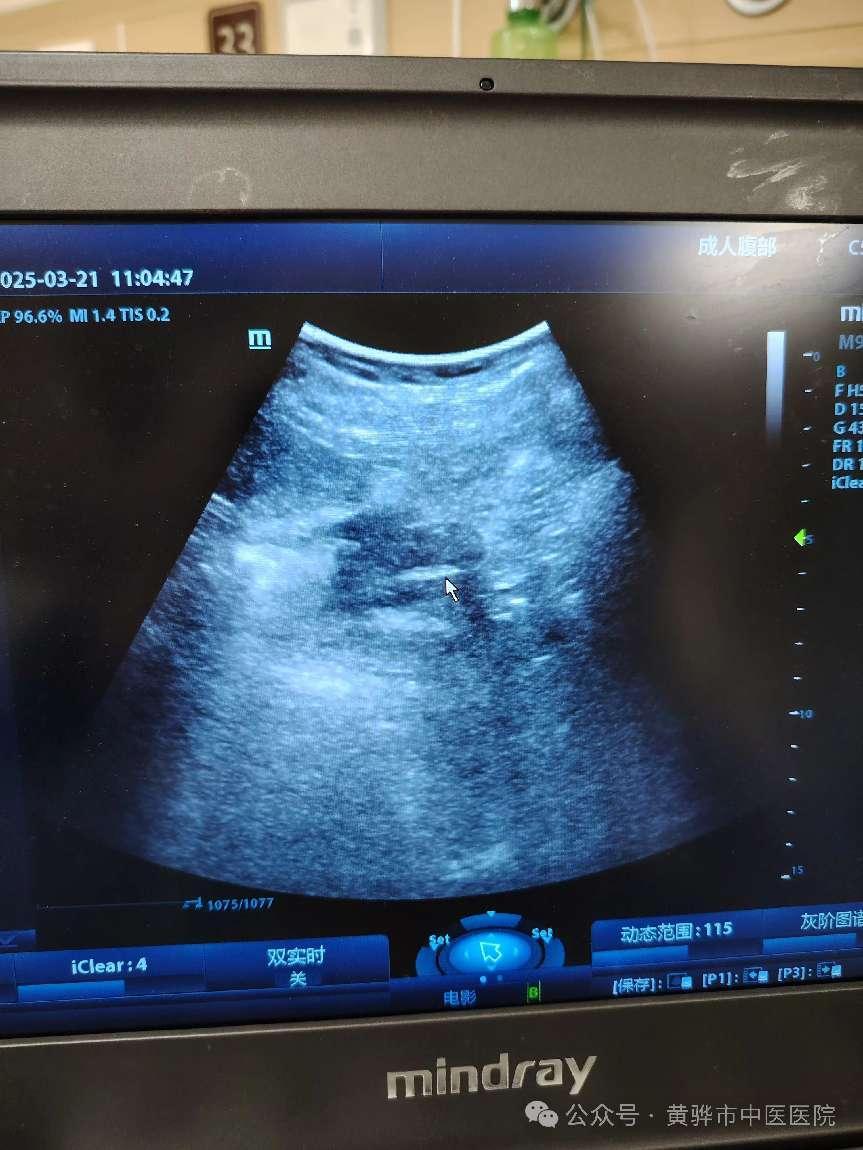

近日,黄骅市中医医院康复科护理团队协同彩超室成功开展了黄骅市中医医院首例彩超引导下鼻肠管置入术,标志着黄骅市中医医院在危重症患者营养支持治疗领域迈出了重要一步。此项技术的成功实施,体现了黄骅市中医医院康复科护理团队以技术创新推动优质护理服务的理念,不仅提升了黄骅市中医医院在临床营养支持治疗中的技术水平,也为危重症患者提供了更加安全、精准的治疗方案。

鼻肠管置入术是危重症患者肠内营养支持的重要手段,尤其适用于无法经口进食或存在误吸风险的患者。传统的鼻肠管置入术多依赖胃肠镜或X线引导,存在操作时间长、患者不适感强等问题。而彩超引导技术的引入,能够实时观察导管位置,显著提高置管的精准性和安全性,减少并发症的发生,为患者提供了更加舒适、安全的治疗体验。